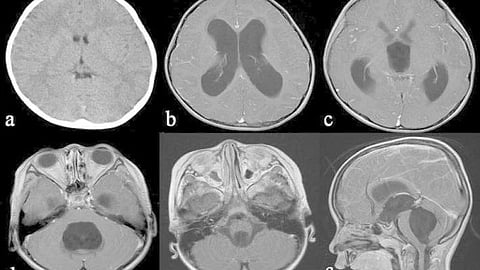

MRI of a tetraventricular hydrocephalus in a 3-year-old boy with an idiopathic fourth ventricle outlet syndrome.

Hydrocephalus is prevalent worldwide and can affect people of any age. Ishi Y, Asaoka K, Kobayashi H, Motegi H, Sugiyama T, Yokoyama Y, Echizenya S, Itamoto K, CC BY 4.0, via Wikimedia Commons